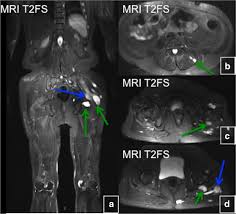

Enchondromas have a characteristic appearance on Magnetic Resonance Imaging MRI as well. Oral Surgery Oral Medicine Oral Pathology Oral Radiology is required for all clinicians involved in the diagnosis and treatment of oral and maxillofacial disease. GeneReviews an international point-of-care resource for busy clinicians provides clinically relevant and medically actionable information for inherited conditions in a standardized journal-style format covering diagnosis management and genetic counseling for patients and their families.

Typically enchondroma is discovered on an X-ray scan. Oral Surgery Oral Medicine Oral Pathology and Oral Radiology Vol. It may predominantly affect the medullary portion andor cortex of bone. Each chapter in GeneReviews is written by one or more experts on the specific condition or disease. And The result of the test will directly impact the treatment being delivered to the member. OMIM174800 is a rare disorder characterized by skeletal lesions skin hyperpigmentation and hyper-functioning endocrinopathies 1 2It arises from post-zygotic gain-of-function mutations in the GNAS gene which encodes the α-subunit of the G s signalling protein These mutations disrupt the intrinsic GTPase. Cafè-au-lait skin pigmentations and endocrine dysfunction such as precocious puberty diabetes mellitus goiter and breast fibroadenomatosis 7 Radiographic features Typically seen as a well-circumscribed intramuscular mass. Oral Surgery Oral Medicine Oral Pathology Oral Radiology is required for all clinicians involved in the diagnosis and treatment of oral and maxillofacial disease. It is the only major dental journal that.